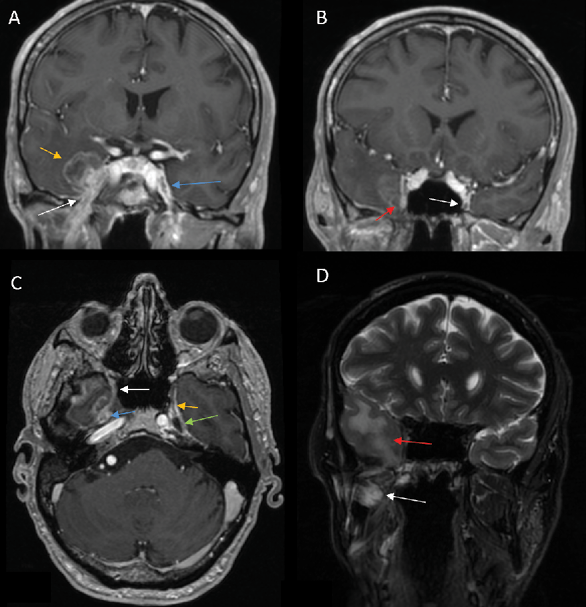

Primary

1) PNS commonly presents as enhancement of the affected nerve, which is attributed to the disruption of the blood-nerve barrier caused by the tumor growth and the associated nerve damage [28]. This enhancement is frequently accompanied by nerve enlargement due to multiple pathophysiological processes including tumor infiltration, inflammation, interstitial edema, and neurotrophic factor-induced hypertrophy [1]. However, in some instances, enhancement may occur without appreciable nerve enlargement, thus creating diagnostic challenges in radiological detection. Magnetic Resonance Imaging (MRI) optimally demonstrates both neural enhancement and enlargement, particularly when extending through neural foramina. Pathologic enhancement is characterized by diffuse, uninterrupted enhancement with no clear demarcation from the Perineural Vascular Plexus (PNVP) (Fig. 1, A, B and C) [2]. Careful evaluation of the enhancement intensity, thickness, and symmetry between the sides is essential to identify pathological changes. On CT, although individual nerves may not be well-defined, excessive contrast enhancement in neural foramina or canals can indicate nerve involvement [29].

Fig. 1. PNS along mandibular and maxillary nerves. A, B, C – 3D T1 ISO sequence with contrast enhancement, D – T2 FSE with fat suppression. A, B, D – Coronal plane, C – Axial plane. A – Perineural spread (PNS) is observed in the right mandibular nerve region, with nerve thickening and contrast enhancement. The foramen ovale is widened (the white arrow) compared to the healthy left side. A tumor is visible medially in the right temporal lobe (the yellow arrow). On the left, the intact mandibular nerve appears hypointense, surrounded by a perineural vascular plexus (the blue arrow). B – Contrast enhancement of the right maxillary nerve in the foramen ovale region (the red arrow). On the left, the intact maxillary nerve is surrounded by a perineural vascular plexus (the white arrow). C – Tumor infiltration of Meckel’s cave on the right side (the blue arrow), with thickening and contrast enhancement of the maxillary nerve, indicating PNS (the white arrow). On the left, Meckel’s cave appears normal with fluid-intensity signal (the green arrow), and the maxillary nerve remains non-dilated and hypointense (the yellow arrow). D – Vasogenic edema is observed in the temporal lobe due to tumor compression (the red arrow), along with signs of acute denervation (hyperintense signal) in the masticatory muscles, most pronounced in the medial pterygoid muscle (the white arrow).

4) On CT or MR imaging, replacement of the fluid signal in Meckel’s cave by a solid and enhancing lesion (Fig 1 C) indicates invasion of the trigeminal cistern [29].

On MRI, denervated muscles undergo a characteristic pattern of change:

In the acute phase (<1 month), MRI findings are characterized by T2 hyperintense edema-like signals, best visualized on fat-suppressed T2-weighted sequences (Fig. 1 D), and contrast enhancement of the affected muscles, which is most prominent on post-contrast, fat-suppressed T1-weighted images. An increased muscle volume is also noted [29]. During the first four weeks of denervation, there is a shift in water distribution, with a relative decrease in intracellular water and a corresponding increase in extracellular water, while the total tissue water remains unchanged. This redistribution leads to hyperintense signals on T2-weighted MR images, mimicking edema, as the T2 relaxation time of extracellular water is longer than that of intracellular water [31]. Additionally, enhanced contrast uptake is observed in the affected muscles due to increased perfusion and contrast medium accumulation in the extracellular space [31]. Notably, the denervated muscle retains its internal striation, distinguishing it from the muscle infiltrated by tumors, which disrupts the muscular architecture [2]. On PET imaging, there is typically increased 18F-FDG uptake in the affected musculature due to hypermetabolism associated with acute denervation [32].